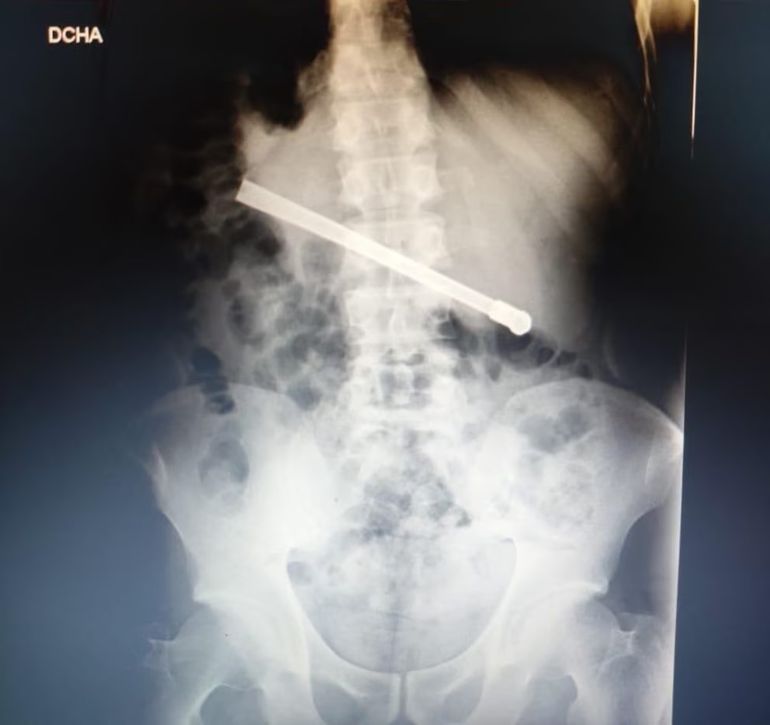

Meses atrás se conoció un caso similar al del interno de Piñero. A mediados del mes de agosto, un detenido que estaba alojado en el Complejo Penitenciario de Rosario, en el extremo oeste de la ciudad, se tragó una bombilla de mate en horas de la noche. Tuvo que ser trasladado al Hospital Eva Perón de Granadero Baigorria, donde fue operado con éxito, ya que los médicos lograron sacarle el elemento.

Identificado como Oscar Fabián Rodríguez (35), tuvo que pedir asistencia médica a causa de una dolencia estomacal, y fue llevado de urgencia hasta el hospital, donde se corroboró en una placa radiográfica que había ingerido una bombilla. El utensillo había quedado atravesado en la zona toracoabdominal.

El presidiario oriundo de Venado Tuerno, luego de haber sido intervenido quirúrgicamente, quedó internado en observación, a la espera de una evolución favorable.